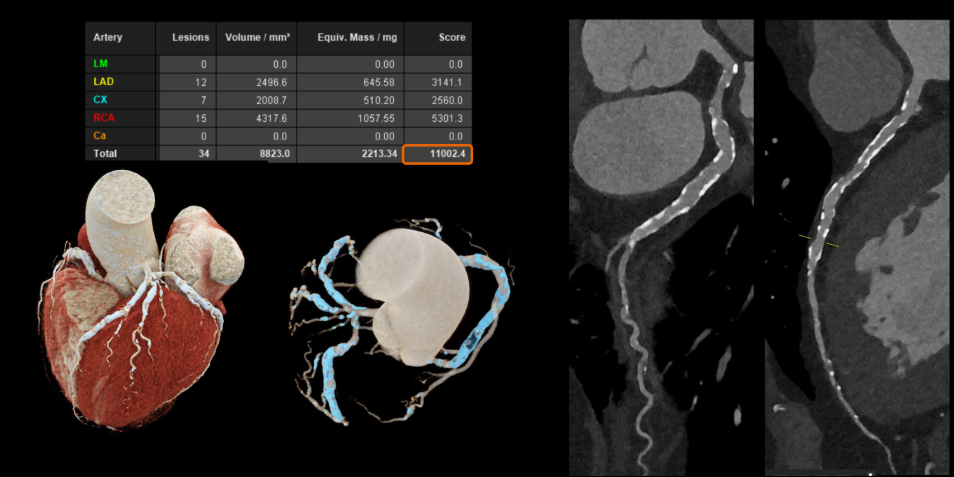

For cardiovascular diseases, especially in patients with stents or severe coronary calcification – cases often challenging to assess with conventional CT – this technology yields clearer images. This allows physicians to visualize vessel lumens and atherosclerotic plaques, even in patients with high heart rates or arrhythmias, without requiring additional medication.

![]() |

Coronary artery images show enhanced clarity, reduced noise, and enable more precise assessment. *Photo: Siemens Healthineers* |